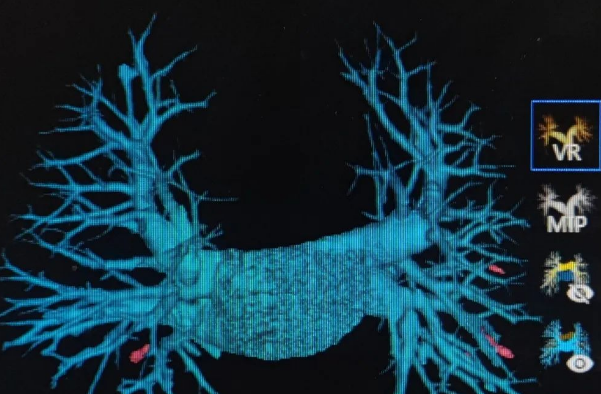

肺动脉CTA检查:守护长期卧床与VTE高危患者的隐形盾牌

2025-05-15